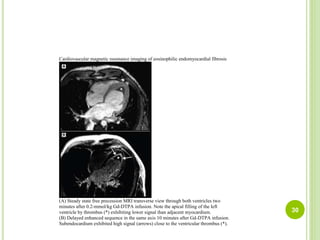

Cardiovascular magnetic resonance imaging of eosinophilic endomyocardial fibrosis

(A) Steady state free precession MRI transverse view through both ventricles two

minutes after 0.2-mmol/kg Gd-DTPA infusion. Note the apical filling of the left

ventricle by thrombus (*) exhibiting lower signal than adjacent myocardium.

(B) Delayed enhanced sequence in the same axis 10 minutes after Gd-DTPA infusion.

Subendocardium exhibited high signal (arrows) close to the ventricular thrombus (*).